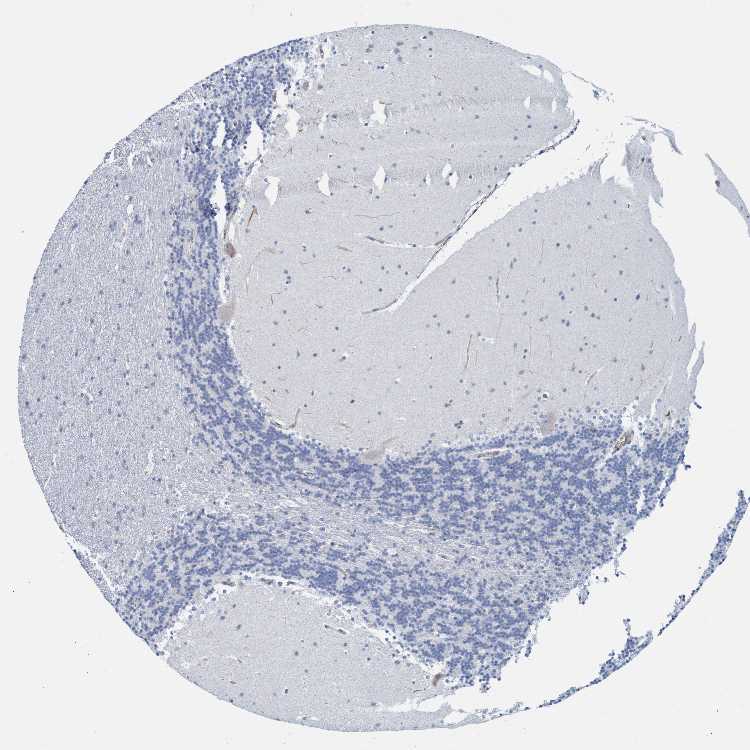

BRAIN CEREBELLUM Show tissue menu

CEREBELLUM - Expression summary

CEREBELLUM - Antibody stainingi

Antibody staining in the annotated cell types in the current human tissue is reported as not detected, low, medium, or high, based on conventional immunohistochemistry profiling in selected tissues. This score is based on the combination of the staining intensity and fraction of stained cells.

Each image is clickable and will lead to virtual microscopy that enables deeper exploration of all samples and also displays staining intensity scores, fraction scores and subcellular localization as well as patient and tissue information for each sample.

Antibody HPA021948Antibody HPA067827

Purkinje cells -Low

Purkinje cells - cytoplasm/membrane Low-

Purkinje cells - dendrites Low-

Purkinje cells - nucleus Not detected-